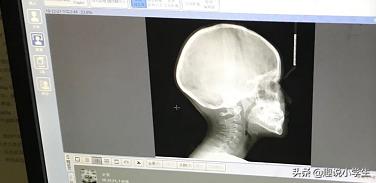

Au bout d'une semaine, je me suis réinscrit auprès de l'orthodontiste de l'hôpital dentaire, qui, après avoir jeté un coup d'œil, a déclaré que la situation était très grave et a immédiatement fait prendre des clichés. Le médecin a déclaré que les incisives permanentes de l'enfant empêchaient l'éruption des incisives et qu'il fallait stimuler le développement de l'os maxillaire tout de suite, c'est-à-dire le traiter tout de suite. Trois mois plus tard, la traction faciale a été ajoutée. L'ensemble du traitement a duré six mois et a coûté plus de 7 000 euros.

Vous trouverez ci-joint les photos avant et après la correction de mon fils. La photo 2 est avant la correction et la photo 3 est après la correction, vous pouvez clairement voir le changement au niveau des lèvres latérales.